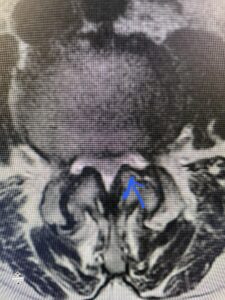

Fig 5 Axial T2-weighted lumbar MRI demonstrating significant L3 inferior facet contribution of severe stenosis (blue arrow)

Another patient is a 62 year-old female with progressive low back pain and right leg pain and numbness that radiates to the top of her foot. She tried physical therapy and epidural injections. MRI demonstrated severe L3-4 stenosis and a grade 1 spondylolisthesis (Fig 4). There was L5-S1 and L4-5 disc collapse with modic end-plate changes. Biomechanically because of the significant degeneration of these disc spaces which stiffened the L4-S1 segment more stress was placed on the L3-4 segment, resulting in significant premature degeneration and compensatory stenosis and segmental instability. The MRI also showed pathologically, because of the slip, the L3 inferior processes were more anteriorly oriented and hence contributing to the majority of the lumbar canal compromise. Note the more sagittally-oriented facets in this case compared to the prior case (Fig 5). The patient underwent a decompressive laminectomy with attention of removing the inferior processes of L3 to fully decompress the canal. We also performed an L3-4 fusion with instrumentation (Fig 6). The patient had an uneventful postoperative course with improvement of leg pain. Of note with relief of the disabling leg pain patients are generally very happy. Patients can often manage their low back pain; it is the leg pain that they just can’t tolerate.